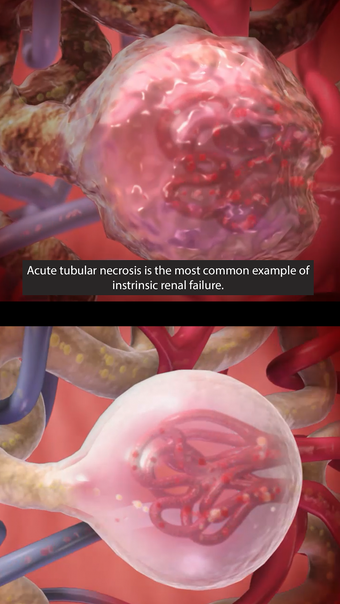

Physiology & Pathology is a comprehensive application that provides an interactive guide to human anatomy. Developed by Visible Body, this Android application is a full version licensed program that falls under the lifestyle category of medical subcategories. With more than 5,800 3D models, 38 animations, 16 illustrations, and 26 quizzes, this application covers 48 physiology topics and 57 conditions, allowing users to explore the step-by-step breakdown of common cardiovascular, renal, respiratory, gastrointestinal, and musculoskeletal processes.

One of the most remarkable features of this application is that it enables users to compare 3D models of normal anatomy with models of common diseases and conditions. Furthermore, users can set the heart rate and visualize conduction in a dissectable, beating 3D heart while following along on an ECG. The application also presents animations that demonstrate the physiological processes of gas exchange, pulmonary ventilation, fluid balance, peristalsis, and more. Interactive lessons walk users through the progression of atherosclerosis, kidney stones, lung cancer, and other common conditions, and quizzes test users' knowledge of various physiological processes and pathologies.